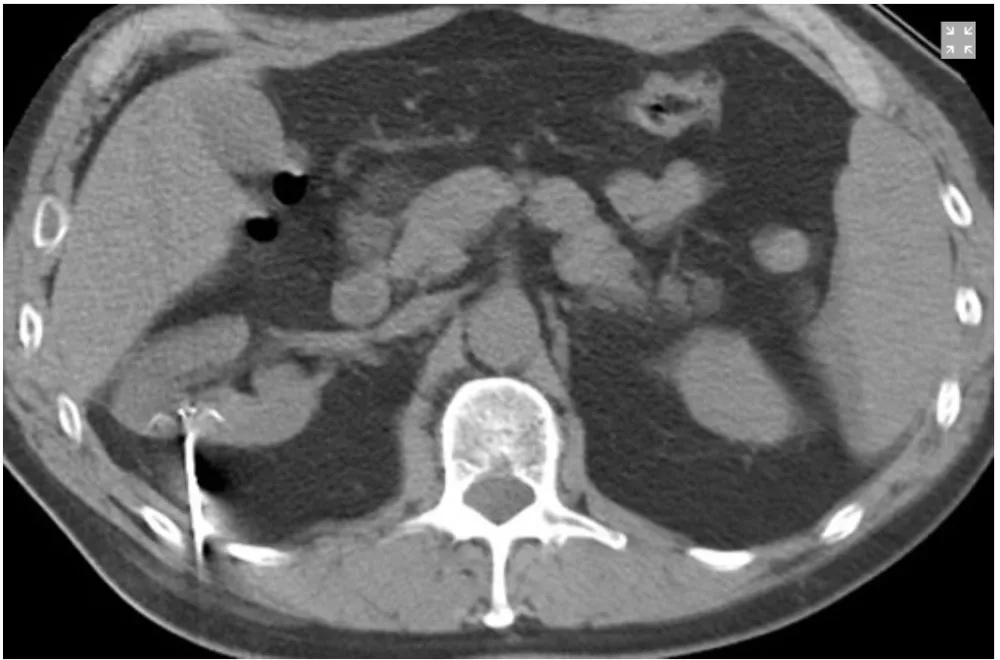

Na imagem 2 é possível identificar a sonda de radioablação.

Nos pacientes múltiplos tumores renais devemos suspeitar imediatamente de Doença de Von-Hippel Lindau, nesses casos devemos procurar tratamentos que visem poupar massa renal, uma vez que a recorrência dos tumores é a regra.